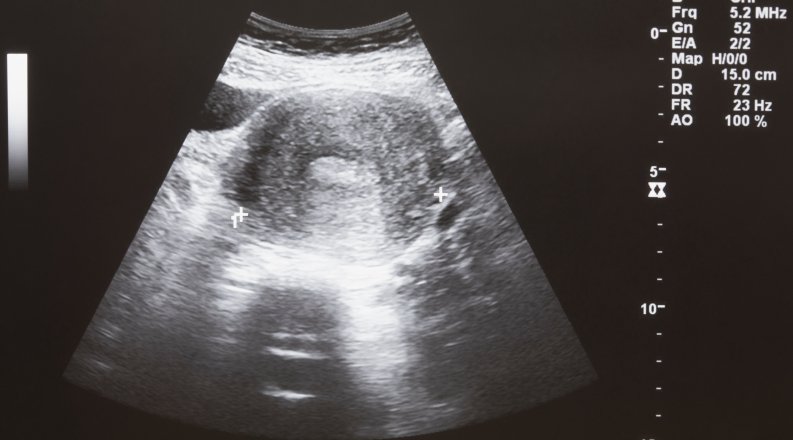

Ultrasound plays a critical role in obstetrical care, helping evaluate fetal health and identify maternal risks like preterm birth and preeclampsia in millions of pregnancies annually in the USA. However, conducting and interpreting ultrasounds requires highly skilled operators and clinicians. By developing AI tools, the process of acquiring ultrasound images and interpreting them accurately could be significantly improved. AI can speed up image capture, improve interpretation accuracy, and even introduce new ways to assess fetal and maternal health using novel measurements and algorithms. Integrating AI into ultrasound practices promises not only to enhance efficiency but also to increase the precision of diagnoses and potentially prevent adverse pregnancy outcomes.

A collaborative initiative by Macon & Joan Brock Virginia Health Sciences at ODU and the School of Data Science aims to harness AI for this purpose. They plan to build a training dataset from a vast collection of ultrasound images gathered over the years. The AI system will analyze these images to develop predictive models, which will then be tested on new ultrasound data. The success of AI predictions will be measured against real-world postnatal outcomes. By applying these AI tools in clinical settings, the project aims to validate their utility, while offering significant benefits with minimal risk. The ultimate goal is to refine these tools to support healthcare providers in delivering more effective obstetrical care.